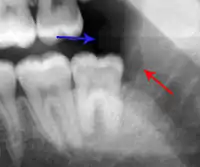

- Radiographs utilized to find dental caries and bone loss laterally or at the apex.

Decay (green) with apical abscess (blue)